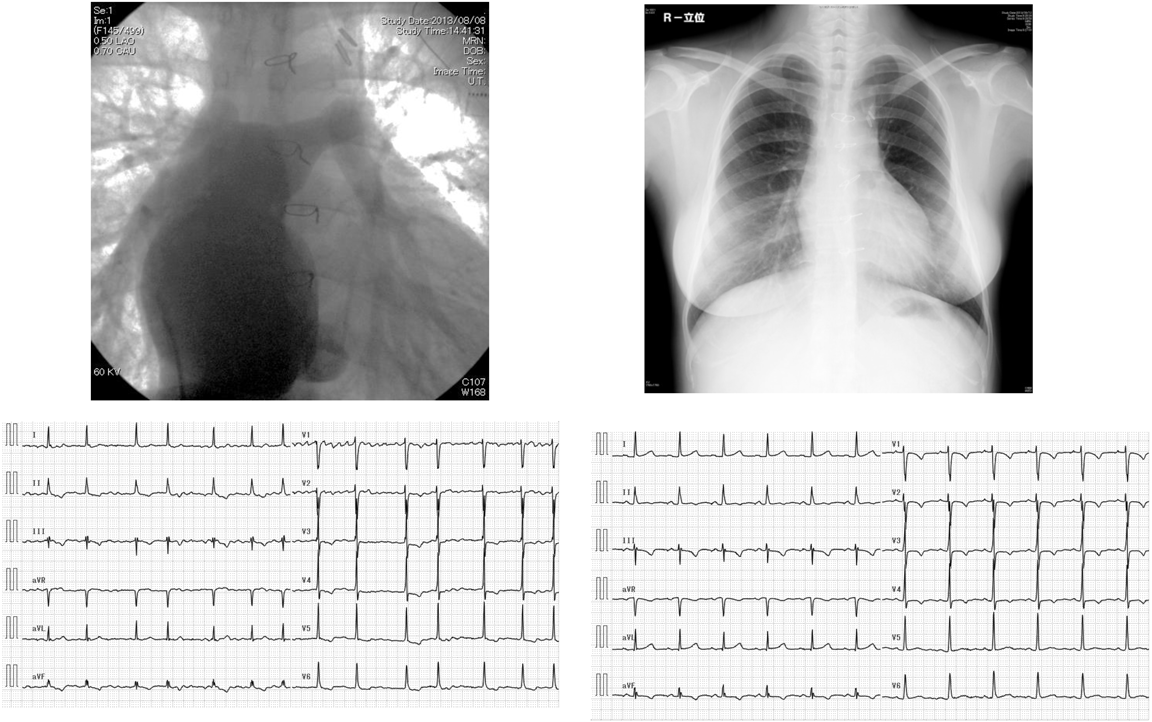

前述のようにAPC Fontanでは右心房に負荷がかかり,瘢痕などを形成することから,複雑な心房性不整脈を来す.近年,血行動態の改善と同時に不整脈を改善させる目的でTCPC conversionが行われるようになった20).傷害された右房壁を切除し,不整脈器質を取り除くことで不整脈を抑えることができる(Fig. 4).施設によっては,TCPC conversion術と同時にMaze手術やペースメーカ植え込みを積極的に行っている.

Pediatric Cardiology and Cardiac Surgery 33(5): 385-394 (2017)

Fig. 4 Fontan conversion from atriopulmonary connection to total cavopulmonary connection. The left upper panel shows an angiogram of the dilated right atrium in a patient with atriopulmonary connection. The left lower panel shows electrocardiogram of atrial fibrillation. The right upper panel shows a chest X-ray after the conversion to total cavopulmonary connection. The right lower panel shows an electrocardiogram of the sinus rhythm